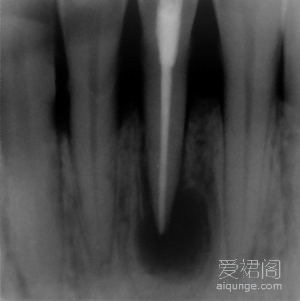

一个典型的根尖囊肿病例,对于这个患者来说,彻底的根管治疗是整个治疗过程的关键。首先,我们对这位患者进行了彻底完善的根管治疗,并要求患者在治疗过程中进行必要的抗炎治疗。患...